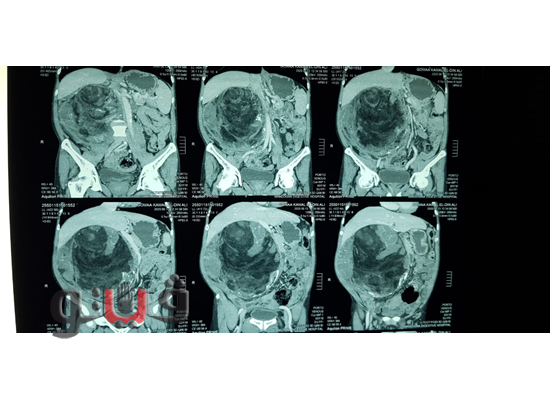

وأشار الدكتور أمجد فؤاد أن المريض ج 0ك يبلغ من العمر 65 عاما من مدينة بلقاس دقهلية وكان يعانى من ورم بالبطن منذ 6 أشهر ولاحظ المريض تضخم حجم البطن من سنة تقريبا وتم استقباله بالمركز من اسبوع وتم اجراء الفحوصات الازمة والاشعة المقطعية والتى أظهرت وجود ورم بحجم كبير بتجويف البطن وضاغط على جميع الأجهزة الداخلية .

وتم اجراء الجراحة واستئصال الورم ويبلغ وزنه 6704 جرامات والمريض حالته الصحية مستقرة وسيتم عمل متابعة للمري بعد تحليل الورم لتحديد نوعه .